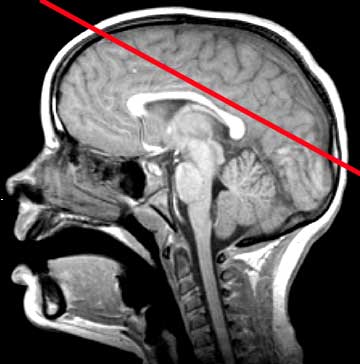

Normal Anatomy

A. Falx Cerebri B. Frontal Lobe C. Body of the Lateral Ventricle D. Splenium of the Corpus Callosum E. Parietal Lobe F. Occipital Lobe G. Superior Sagittal Sinus